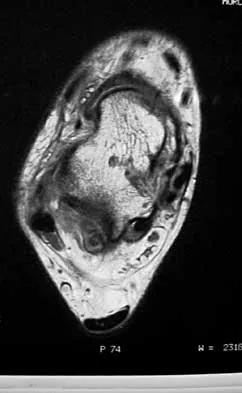

Figures 35a and 35b show the axial T2-weighted and coronal T1-weighted MRI scans of a patient who has enlargement of the right thigh. What is the most likely diagnosis?